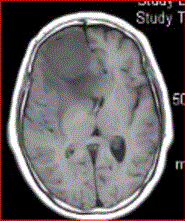

问题 女,64岁,发作性意识丧失,左侧肢体无力,MR显示右侧额叶等T1信号影(下图),病变明显强化,最可能的诊断是

选项 A.室管膜瘤 B.星形细胞瘤 C.脊索瘤 D.脑膜瘤 E.转移瘤

答案 D